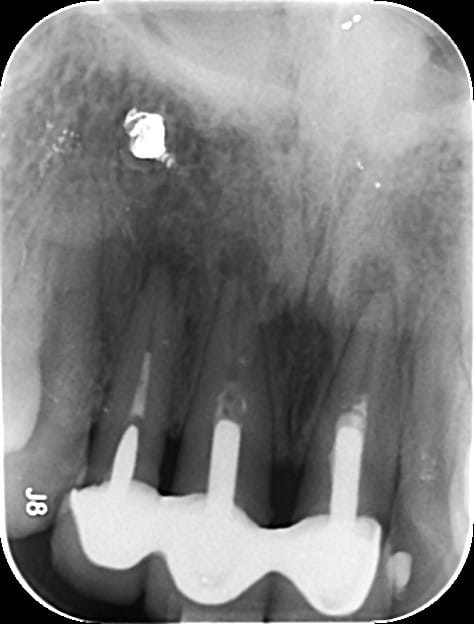

Il s'agit de dents solidarisées faites au cambodge il y à 3 ans .

De grosses recessions et un saignement au sondage tres important l'ont amenés a consulter.

Pour la 22 pas de probleme par contre sur la 11 et la 21 j'ai vraiment peur de tout peter en demontant l' IC .

Quand je vois les esquisses d'endo, je me dis que ça n'a pas dû être scellé dans les meilleures conditions du monde, ça aidera peut-être...

Les infrastructures metales n'ont pas l'air étanches. Si le bridge était nickel j'aurais proposé chir à retro chez un endo exclusif. Mais là le bridge est à refaire, avec les risques que l'on connait et dont la patiente est consciente.